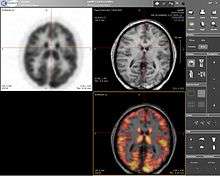

Positron emission tomography–magnetic resonance imaging (PET-MRI) is a hybrid imaging technology that incorporates magnetic resonance imaging (MRI) soft tissue morphological imaging and positron emission tomography (PET) functional imaging.[1]

Presently, the main clinical fields of PET-MRI are oncology,[2][3][4] cardiology[5] and neurology.[6][7][8] Research studies are actively conducted at the moment to understand benefits of the new PET-MRI diagnostic method. The technology combines the exquisite structural and functional characterization of tissue provided by MRI with the extreme sensitivity of PET imaging of metabolism and tracking of uniquely labeled cell types or cell receptors. There is discussion and investigation into utilizing PET-MR with Ion Therapy for the purpose of cancer treatment.[9] with[10][11] MRI's ability to accurately depict the proton density of tissue is a good match for the benefits and technical challenges of treatment planning utilizing Ion Therapy systems.